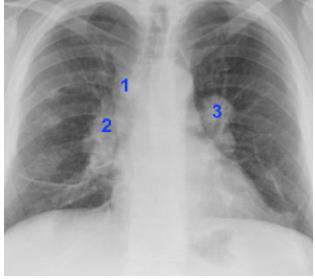

Sobre a radiografia torácica, o sinal do 1-2-3 está relacionado à linfonodopatia da sarcoidose nas regiões:

Enunciado 3621809-1